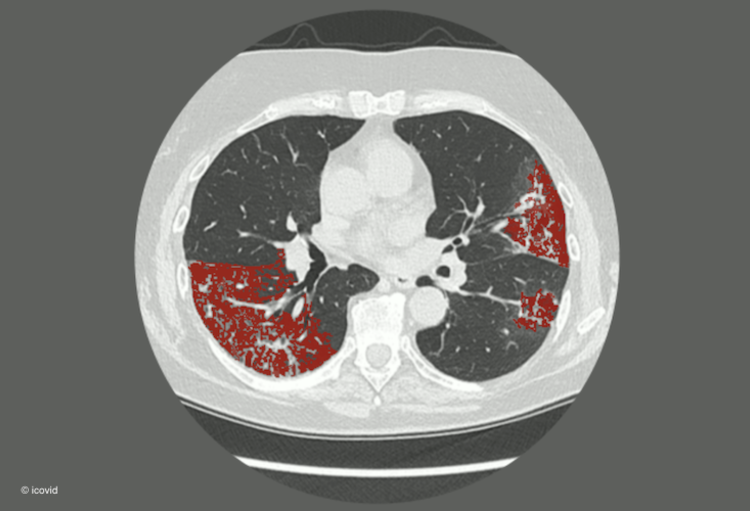

Bij de uitbraak van de coronapandemie in maart werd door de initiatiefnemers van icovid gekeken naar artificiële intelligentie om bij longscans verdachte letsels en dus een mogelijk covid-19-besmetting op te sporen. Het resultaat was de tool icolung, een nieuw triagemiddel.

Dankzij het Belgische initiatief "icovid" en haar toepassing "icolung" werd het in onder meer het UZ Brussel mogelijk gemaakt om longscans in te zetten als een triagemiddel voor mensen die besmet zijn met covid-19. De toepassing die werd ontwikkeld door het UZ Brussel, KULeuven, icometrix en ETRO, een imec onderzoeksgroep van de VUB is een succes en wordt daarom uitgerold over heel Europa.